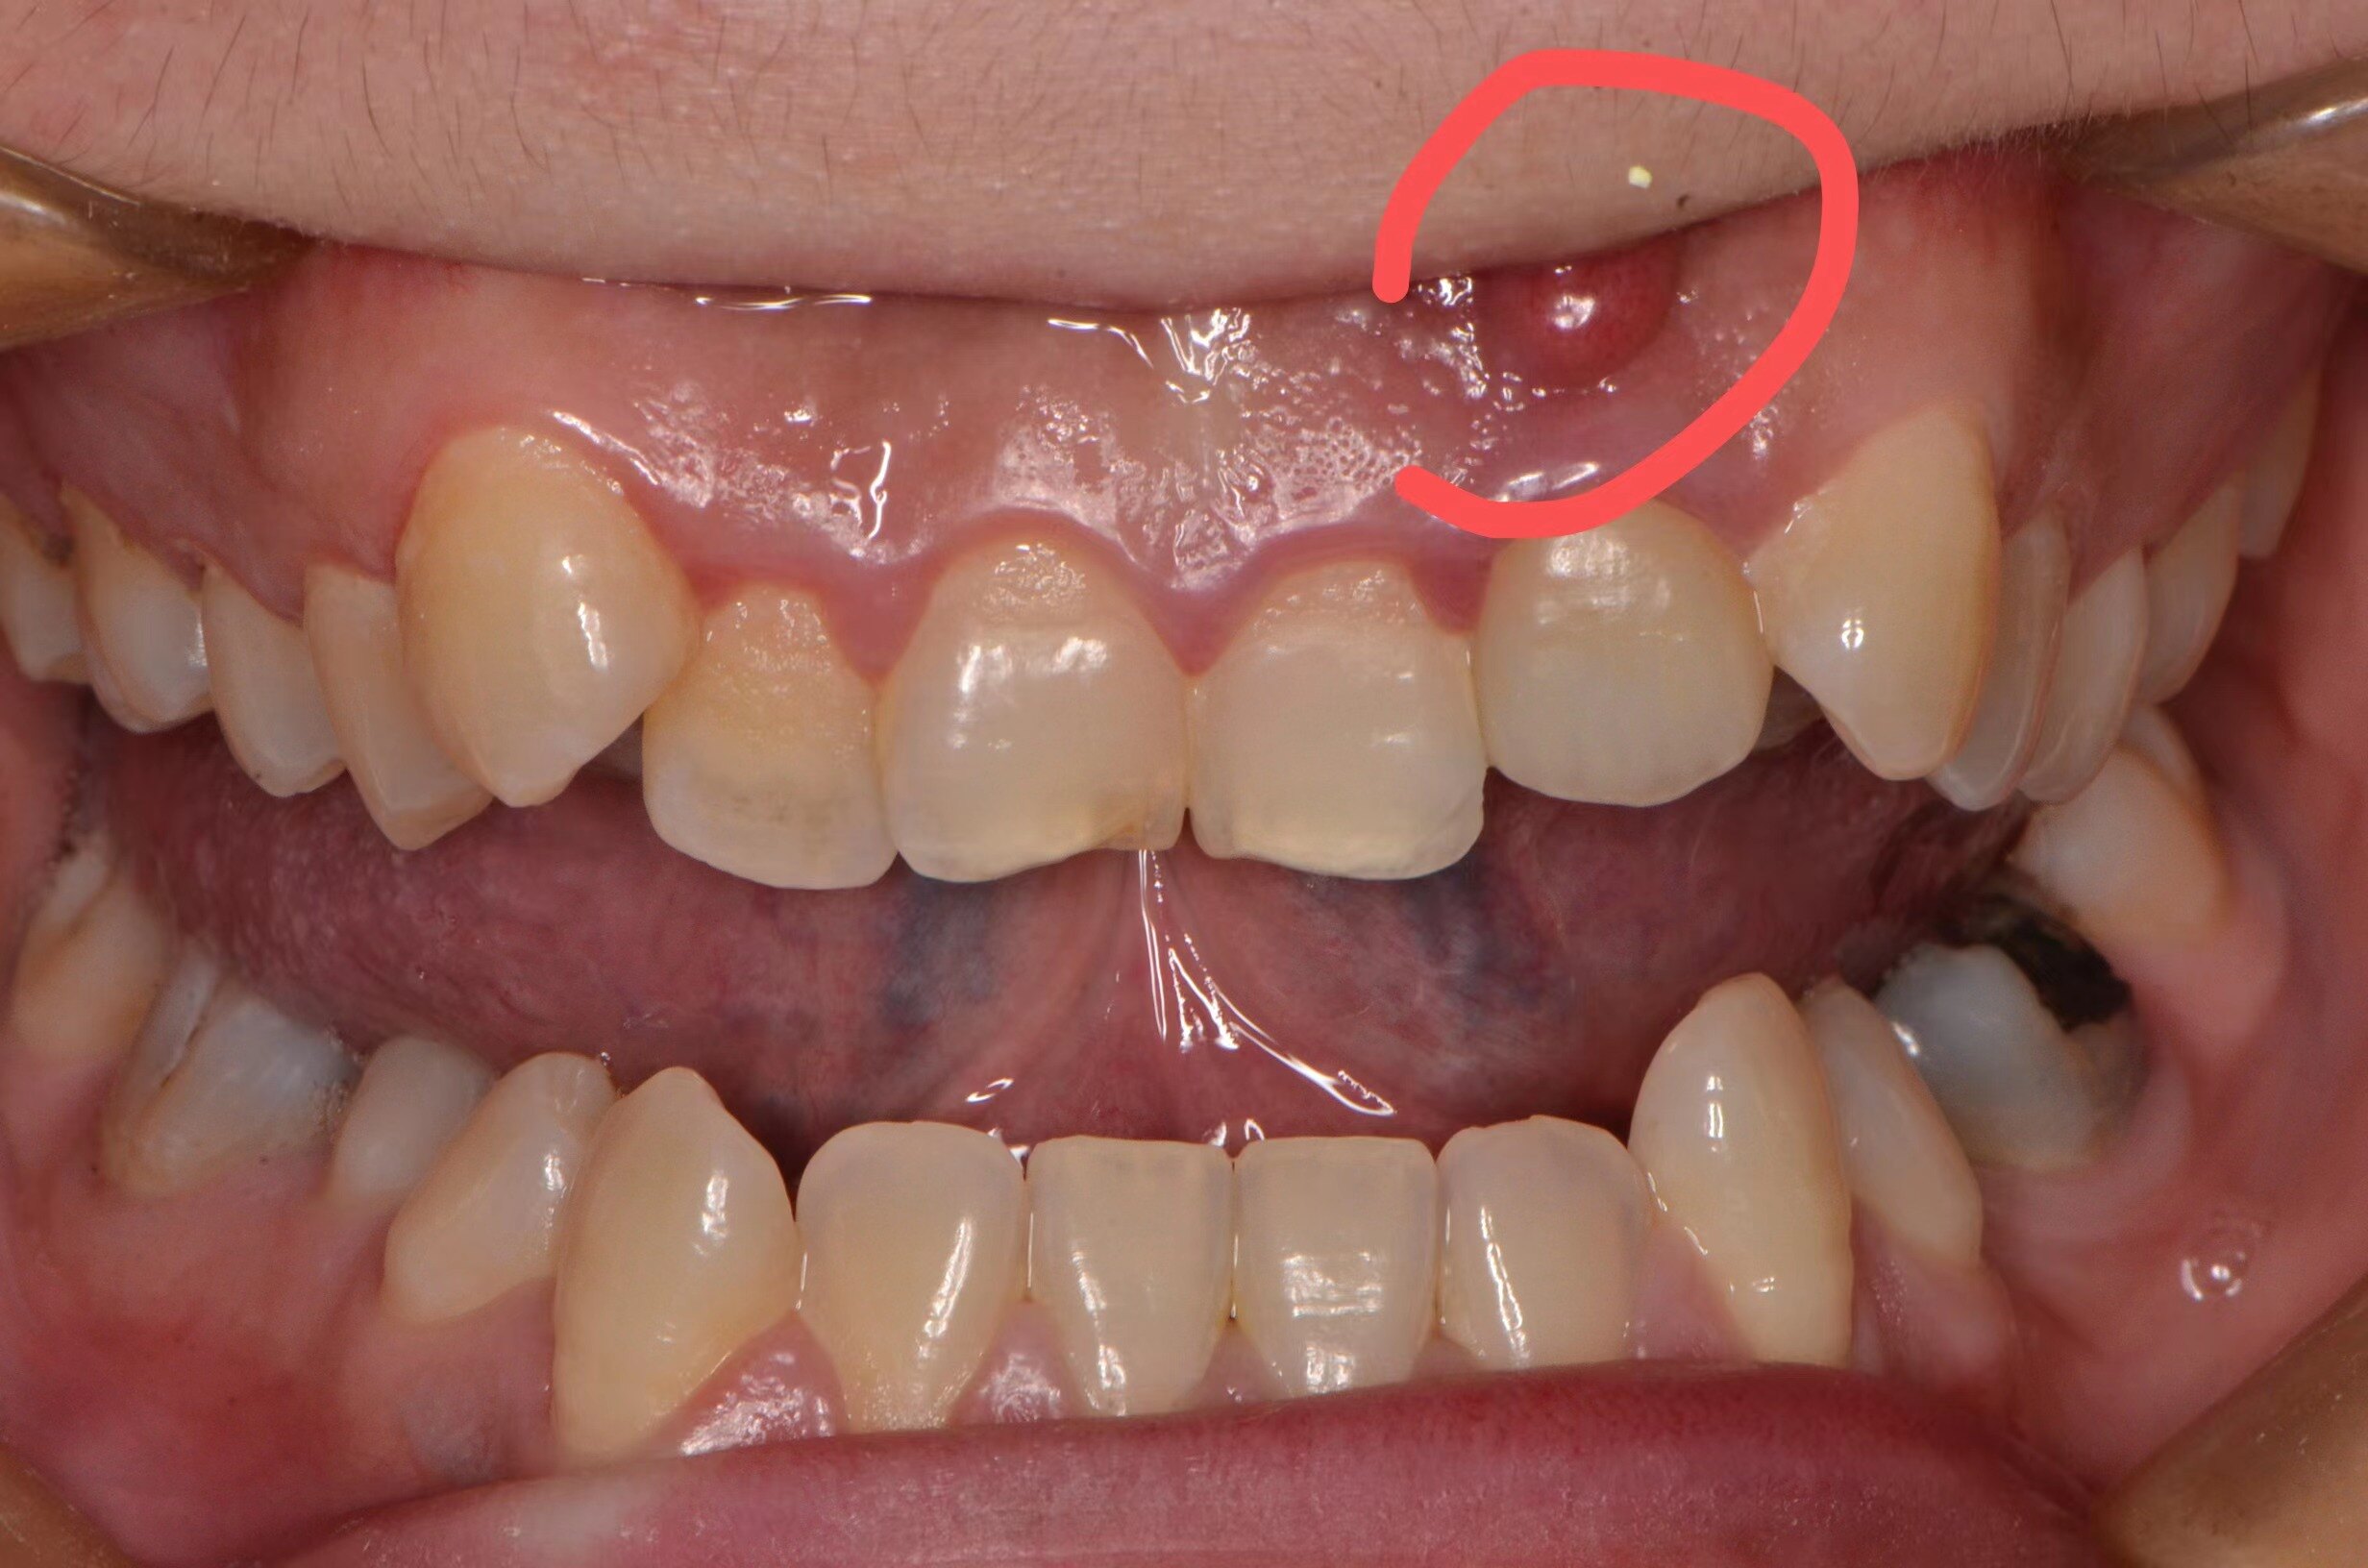

牙齦上的小包不要忽略(溢膿,紅腫,不是上火,可能是根尖周炎)

有些人,牙齒疼的時候,吃不下飯,睡不著。然后,突然不疼了。就覺得好了。其實,反而是病情變嚴(yán)重了。今天這位姑娘的牙齒就是這樣,牙齦一個大包,反而不疼了。其實,壞掉的牙神經(jīng),等于把牙齦下面的骨頭,腐蝕了一個大洞。所以,牙齦上的小包,不要大意。再不看,這個大洞,要往上,會影響鼻咽,甚至上頜骨了。。。